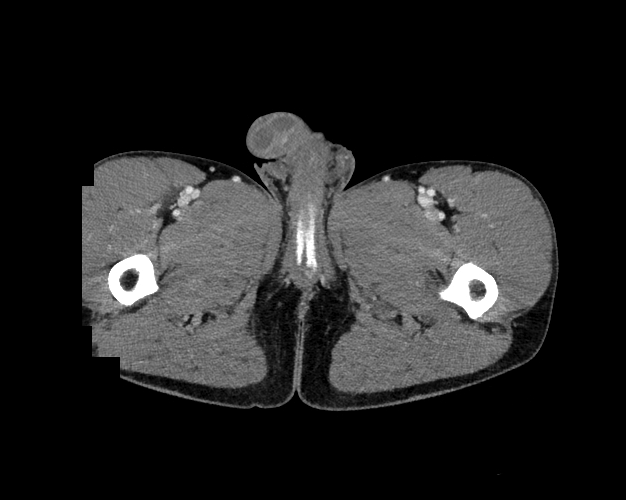

Pelvis

Covers pelvic MRI anatomy.